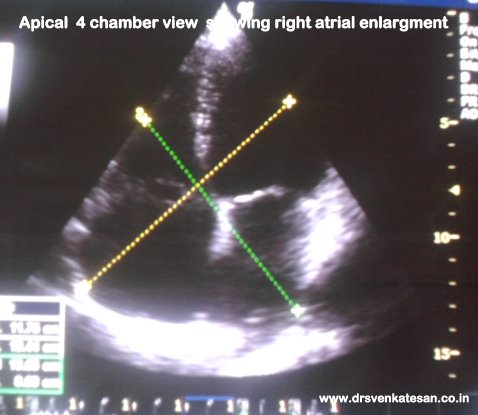

More important  is the impact of right atrial enlargement on the CT ratio. Here was a  patient referred to echo lab for evaluation of cardiomegaly

The right atrium was huge and measuring  more than 5 cms . This increased the CTR.

The following illustration  tries to create echo equivalent of transverse CT diameter by rotating apical 4 chamber view by 90 degrees.

The right and left atrium was significantly dilated . This patient had atrial fibrillation and the atrial enlargement was due to chronic AF.